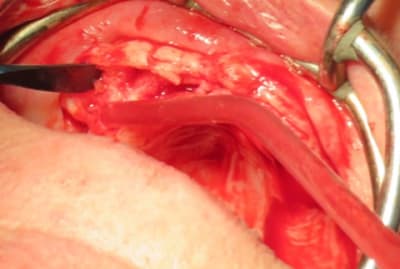

voici ce qui a été fait par un chirurgien maxillo en AG qui avait à son actif une vingtaine d'implants posés, la S.I.A.O (17), pose des guides à appuis osseux (18, 19), résultat fin de chirurgie (20).